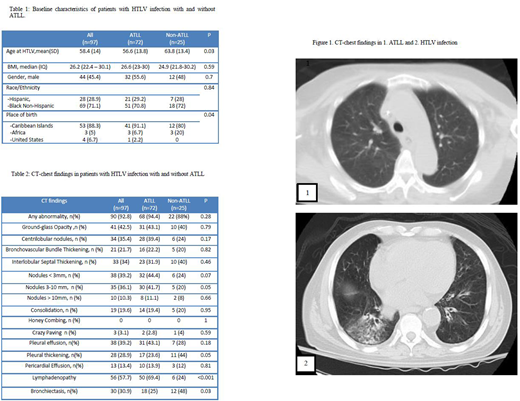

Results: A total of 97 patients (72 with ATLL and 25 with HTLV alone) were identified. Mean age at HTLV diagnosis was 58.4 years (range: 33-88), 54.6% were females, 72.2% were Black Non-Hispanics while 27.8% were Hispanic. 88.3% were from Caribbean origin. Smoking history was similar between ATLL and non-ATLL groups (12% vs 8%, p=0.07) with no cases of prior active TB infection. Abnormal CT chest findings were present in 92.8%, 94.4% and 88% for the total cohort, ATLL and non-ATLL patients.

Among patients with ATLL, 52.1% had acute and 43.7% had lymphomatous types; while only 1.4% and 2.8% had smoldering and chronic type. The most common CT chest findings were lymphadenopathy (50, 69.4%); followed by 3-10 mm nodules (32, 44.4%), ground-glass opacity, pleural effusion (31, 43.1% each), centrilobular nodules (28, 39.4%), thickening of interlobular septum (23, 31.9%) and bronchiectasis (18, 25%). Compared to the acute subtype, patients with lymphomatous subtype had higher rates of lymphadenopathy (83.9% vs 64.9, p=0.07) and lower rates of bronchiectasis (16.1% vs 35.1%, p=0.07).

Among patients with non-ATLL, HTLV infection was diagnosed at an older age (63.8 vs. 56.6 years, p=0.03); HTLV-associated comorbidities were found in 16 cases (64%). Of these, myelopathy was the most frequent (10, 40%), followed by strongyloides (4, 16%). After HTLV diagnosis, CT chest was indicated in 28% patients for otherwise unexplained respiratory symptoms and to evaluate lung nodules or other chest X-ray abnormalities in 24% of cases. Bronchiectasis was the most common finding (12, 48%) followed by pleural thickening (11, 44%), ground-glass opacity and thickening of interlobular septum (10, 40%, each). Persistent abnormalities on follow-up imaging were present in 86.7% of the cases. Among patients with HTLV infection, those with ATLL were more likely to have nodules and lymphadenopathy (41.7% vs 20%, p=0.05 and 69.4% vs 24%, p<0.001, respectively) while bronchiectasis and pleural thickening was more likely in patients without ATLL (48% vs 25%, p=0.03 and 44% vs 23.6%, p=0.05; respectively).

Conclusions: Pulmonary findings are highly prevalent in CT chest of patients with HTLV infection with and without ATLL. Bronchiectasis and pleural thickening was more frequently encountered in non-ATLL patients while lymphadenopathy and nodules were common finding in patients with ATLL. Pulmonary involvement in lymphoma is usually characterized by nodules and lymphadenopathy but patients with ATLL had a higher incidence of findings including ground glass opacities, bronchiectasis and interlobular septal thickening possibly due to their underlying HTLV infection. Based on this data, nodules and lymphadenopathy should be classified as ATLL involvement of the lung while other findings described here could be due to HTLV infection. These findings are important in staging and response criteria for ATLL.